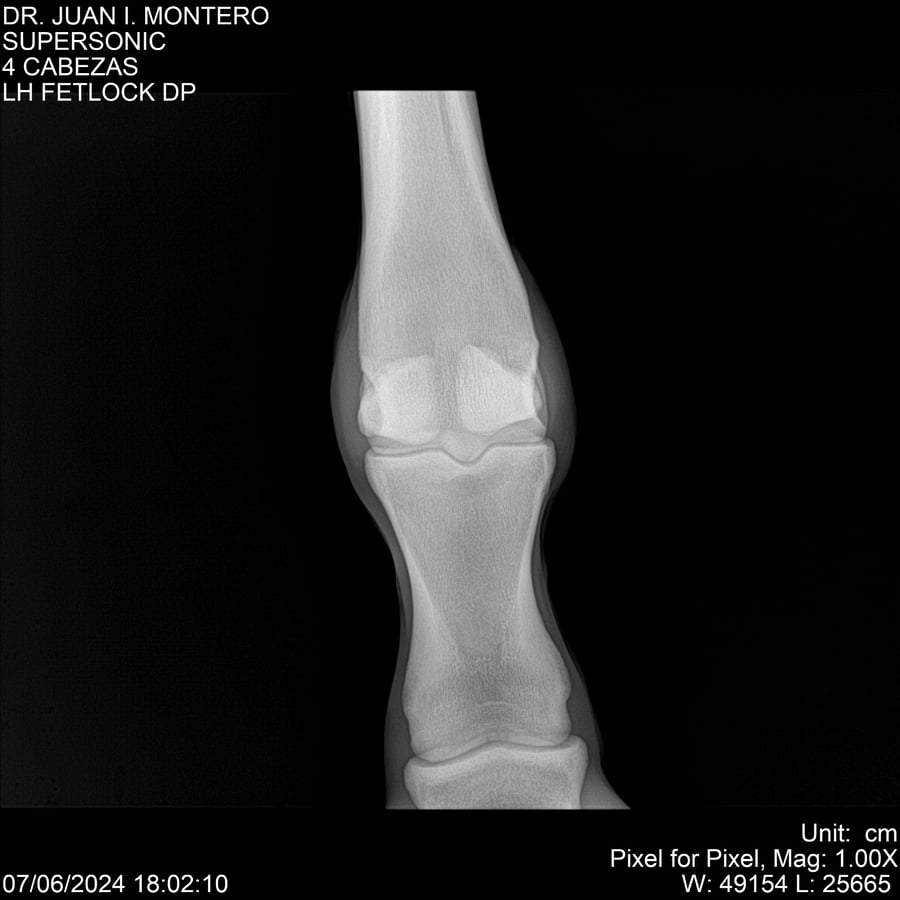

LOTE 5, SUPER SONIC Lote Anterior Volver al remate Lote Siguiente Ficha Contacto Montevideo - Ficha del Lote Identificador: #281089 Categoría: Yeguarizos Montevideo - 69 Visualizaciones ClicData Contacto Empresa: Abelenda N. R., Walter Hugo Nombre*: Teléfono* : E-mail* : Mensaje Enviar Registrese gratis Este contenido Exclusivo está disponible sólo para usuarios registrados Ingresar